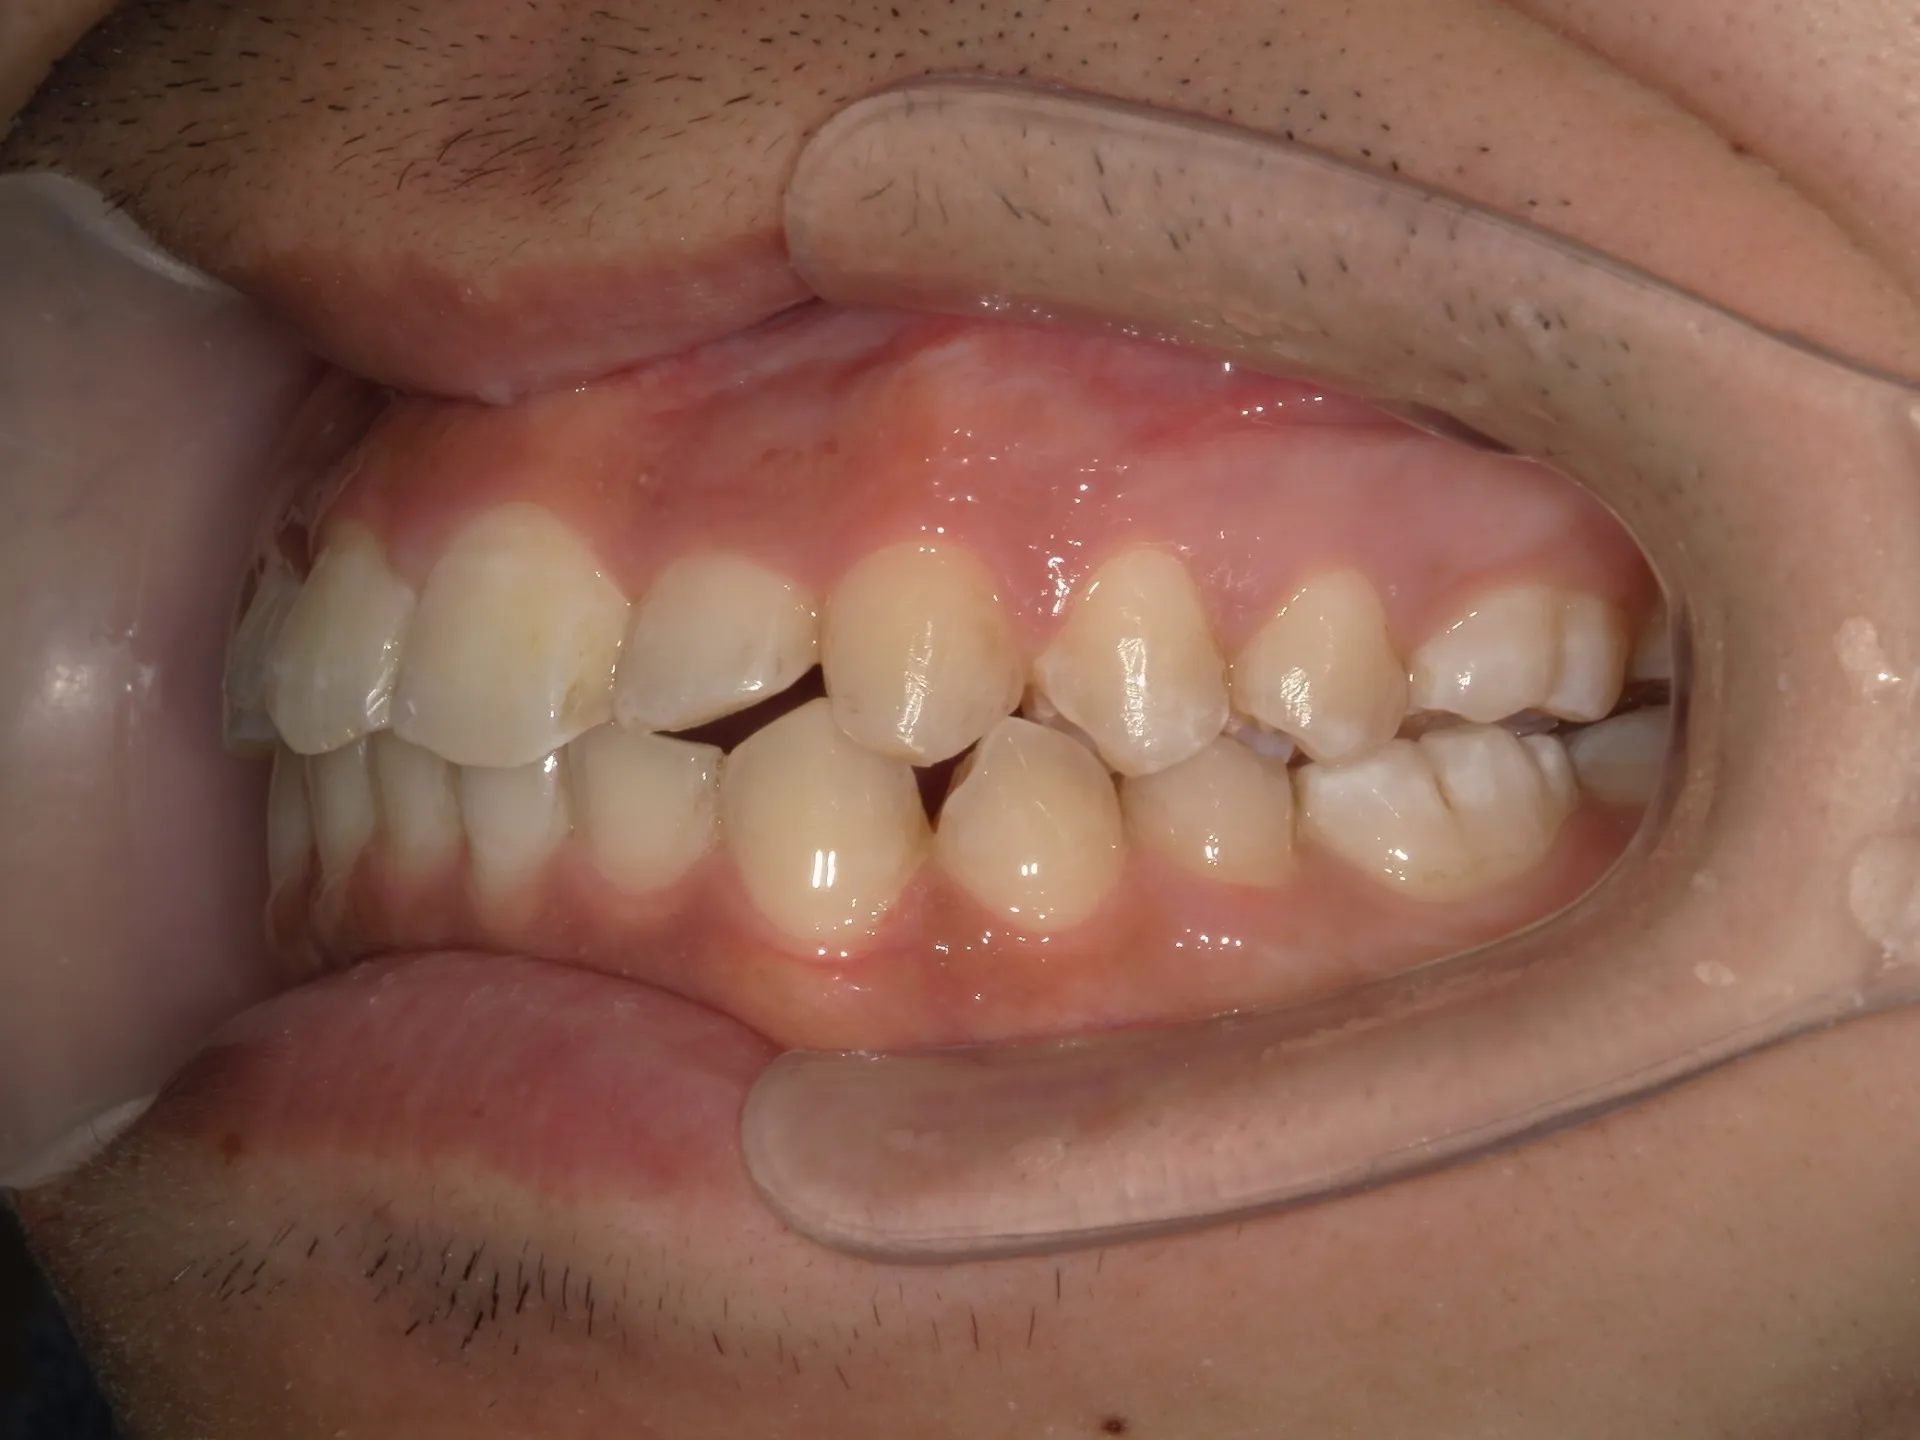

今回は他院さんでインビザライン矯正治療を受けていた患者様を引き継いで当院でインビザライン治療を継続した症例をご紹介致します。

今回はマウスピース矯正を主軸にした矯正ですが、一部ワイヤー矯正も併用して改善しております。

マウスピース矯正のみしか行っていない歯科医院では対処しきれない場合もあり、ワイヤー矯正とマウスピース矯正どちらも行える歯科医院で矯正治療を始めることがきれいな歯並びに近づける方法です。